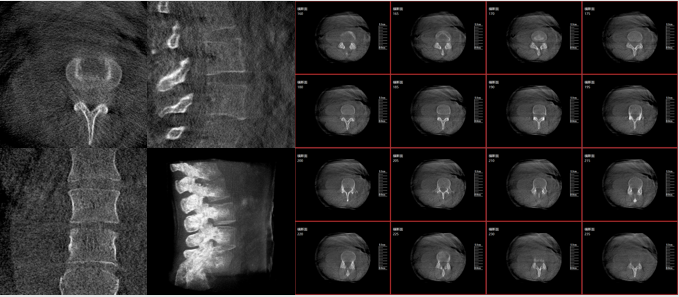

移動式三維C形臂,又稱骨科三維C臂,就是將傳統(tǒng)二維與“類CT模式”相結(jié)合的升級版C形臂,能在術(shù)中快速地生成橫斷面、矢狀面、冠狀面斷層圖像和三維立體圖像。通過不同方位的斷層圖像,能夠更清晰、完整地顯示椎體及其附件的解剖學(xué)結(jié)果,直觀地分析病變與周圍組織的立體空間關(guān)系,三維斷層成像能夠使手術(shù)模擬和手術(shù)方案的制定更加準(zhǔn)確。

術(shù)中三維影像

而三維影像的MPR圖像組可以通過不同平面的切分,使成像區(qū)內(nèi)更豐富的信息得以呈現(xiàn)。尤其是二維影像無法涉及的橫斷面,提供了另一個空間維度的信息量。

在MPR圖像中,冠狀面、矢狀面和橫斷面的信息大大提高了醫(yī)生對于病灶區(qū)以及手術(shù)效果的判定。